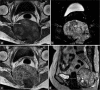

(a-c) Contrast MRI pelvis. A lobulated sacral mass with T1-weighted isointense and T2-weighted hyperintense signal showing mild contrast enhancement. (d) Contrast MRI pelvis. It invaded the right sacroiliac joint and the right ilium (white arrow). There was also involvement of the left sacroiliac joint (white dotted arrow).

(a-c) Contrast MRI pelvis. Expansile pelvic mass centred at the sacrococcygeal junction showing a low to intermediate T1-weighted signal with presence of T1-weighted hyperintense foci indicating intralesional haemorrhage or proteinaceous contents high T2-weighted signal on fat-saturation images and moderate heterogeneous contrast enhancement. (d) Contrast MRI pelvis. Preserved intervening fat plane with the rectum anteriorly (white arrow). Focal breaching of tumour capsule invading into subcutaneous fat posteriorly (black arrow).